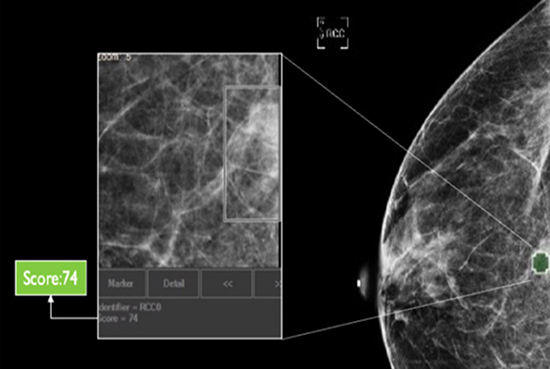

Which Patient to Spend More Time on?

The software also generates a unique, data-driven neuScore™ that provides radiologists with a quantitative measure of suspiciousness in a marked region of interest, ranging from 0 (least suspicious) to 100 (highly suspicious). This score can be tracked over time to evaluate the stability or evolution of identified anomalies.